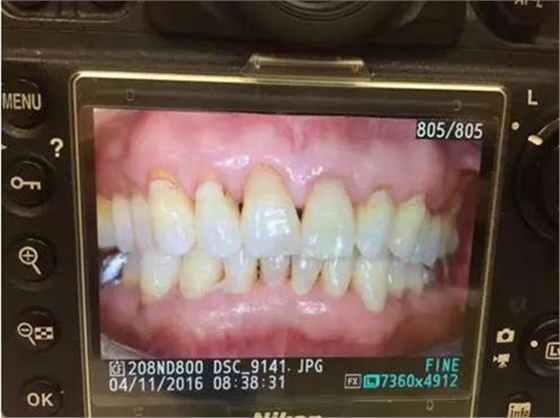

我們最常見的老人是左邊的樣子:滿頭白發(fā),布滿皺紋的臉以及西剩下不多的牙齒。吃東西只能吃軟的或者喝粥,營養(yǎng)很成問題。而如果我們能從年輕時(shí)定期洗牙,最后我們的牙齒都不會棄我們而去。右邊是一位八十歲的老頭,他從年輕時(shí)就開始堅(jiān)持定期洗牙,現(xiàn)在嘴里一顆牙都不缺失。單從這個(gè)照片很難想象這是一個(gè)80歲老人的牙齒吧。所以放心吧,洗牙不會把你的牙洗掉,只會讓你的牙更堅(jiān)固。